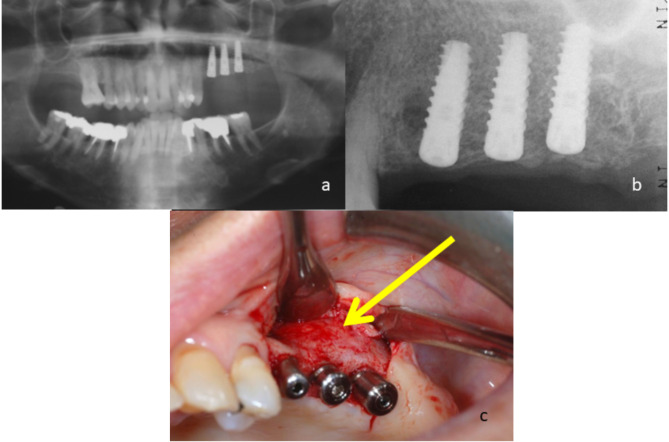

Objectives: Perforation of the Schneiderian membrane (SM) is a common intraoperative complication of sinus augmentation. This study aimed to evaluate risk factors for SM perforation, and to compare clinical outcomes between patients with SM perforation repaired using crosslinked collagen membranes (CLM) compared to those with an intact SM.

Methods: A retrospective cohort study was conducted at a single tertiary medical center. Data was collected on patients requiring sinus augmentation via lateral approach prior to implant placement. The collected data included demographics, surgical details, implant outcomes, radiographic analysis, and presence of SM perforation. In cases of perforation a CLM was used to repair the SM. Statistical analysis was performed to evaluate risk factors for perforation and whether SM perforation repair using CLM influenced early implant failure (EIF). A p-value < 0.05 was considered significant.

Results: Data on 194 individuals who underwent 278 lateral approach sinus augmentation procedures was collected. SM perforation occurred in 66 (23.74%) sinuses. Treatment of SM perforation using CLM yielded similar results to sinuses without perforations: EIF and the augmented gained bone did not correlate with SM perforation. Younger patients, and thick SMs (> 3 mm) had significantly lower risk of perforation.

Conclusions: Older age and thinner SMs are risk factors for sinus membrane perforations. No significant differences in bone gain and EIF were found between perforated and intact membranes.

Clinical relevance: Schneiderian membrane perforation repair using crosslinked collagen membrane provides comparable results to sinus augmentations without perforations, demonstrating its effectiveness in preventing complications.